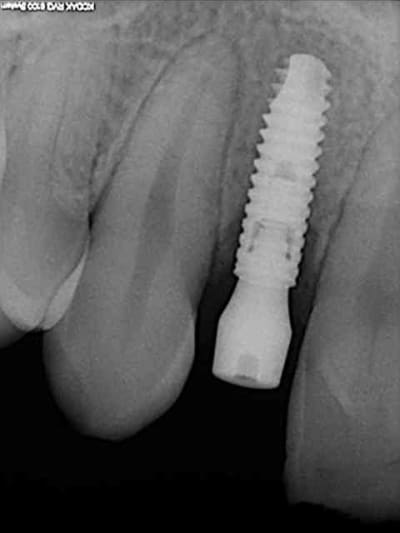

tes implants 12 et 13 n'ont pas le même niveau d'enfouissement, tu n'as pas peur d'une lyse osseuse de 13 pour venir au niveau du col de 12 ?

-1 ou 2 mois plus tard ( je sais plus)

- empreinte avec transfert pop in

- pilier zircone esthétique Axiom

- prothèse et pilier

- pilier zircone en place

- couronne en place (petite compression gingivale)

fin du traitement